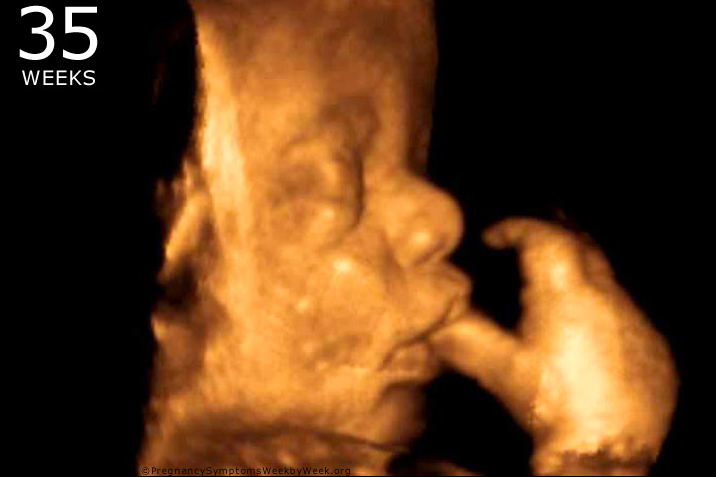

“On this day of prayer and penance, we call to mind the essential truth that every human being possesses an inalienable dignity. We praise God, our Creator, whose plan for human flourishing begins in the womb and provides the foundation upon which a healthy and just society thrives. We also cry out to the Lord for mercy upon a culture that too often fails to recognize the sacredness of human life in its most vulnerable stages of development.

“Positive medical advances and generous acts of charity remain signs of hope. Yet, thousands of unborn children still lose their lives each month, and countless mothers, fathers, and families continue to be wounded by the tragedy of abortion. While official reports demonstrate a decline in abortion in Florida since the Heartbeat Protection Act, which extends crucial protections to children at about six weeks of gestation, there is concern that illicit chemical abortions have risen. Increased availability of abortion drugs not only disregards the fate of the unborn child but also the physical and psychological risks posed to women and minor girls. While the number of abortions taking place is uncertain, what is clear is that much work remains to protect against abortion.

“Human life at every stage of development reflects the image and likeness of God and must never be diminished or discarded. The destruction of unborn life is a grave wrong inflicted on the most defenseless and weak among us, and on society itself. Let us remedy this injustice and ask the Lord to deepen our conviction in the value of every life.”